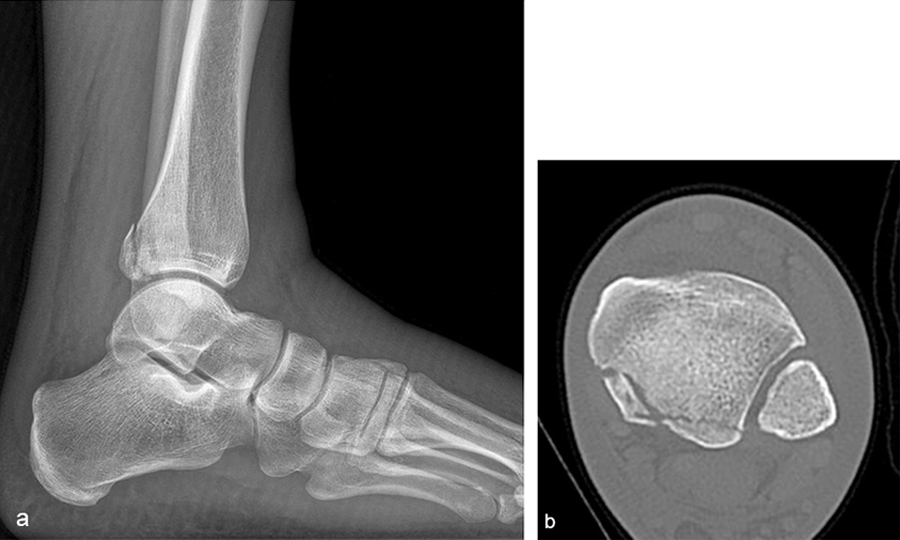

A 27-year-old man fell from a ladder sustaining a proximal fibula fracture (Fig 1) with a multipart posterior malleolar fracture (Fig 2). The patient was treated operatively with direct reduction and plate fixation of the posterior malleolar components. Intraoperative testing demonstrated continued syndesmotic instability requiring fixation (Fig 3). The syndesmosis was reduced in direct fashion and stabilized with a provisional K-wire and clamp before insertion of a FIBULINK Implant (Fig 4).